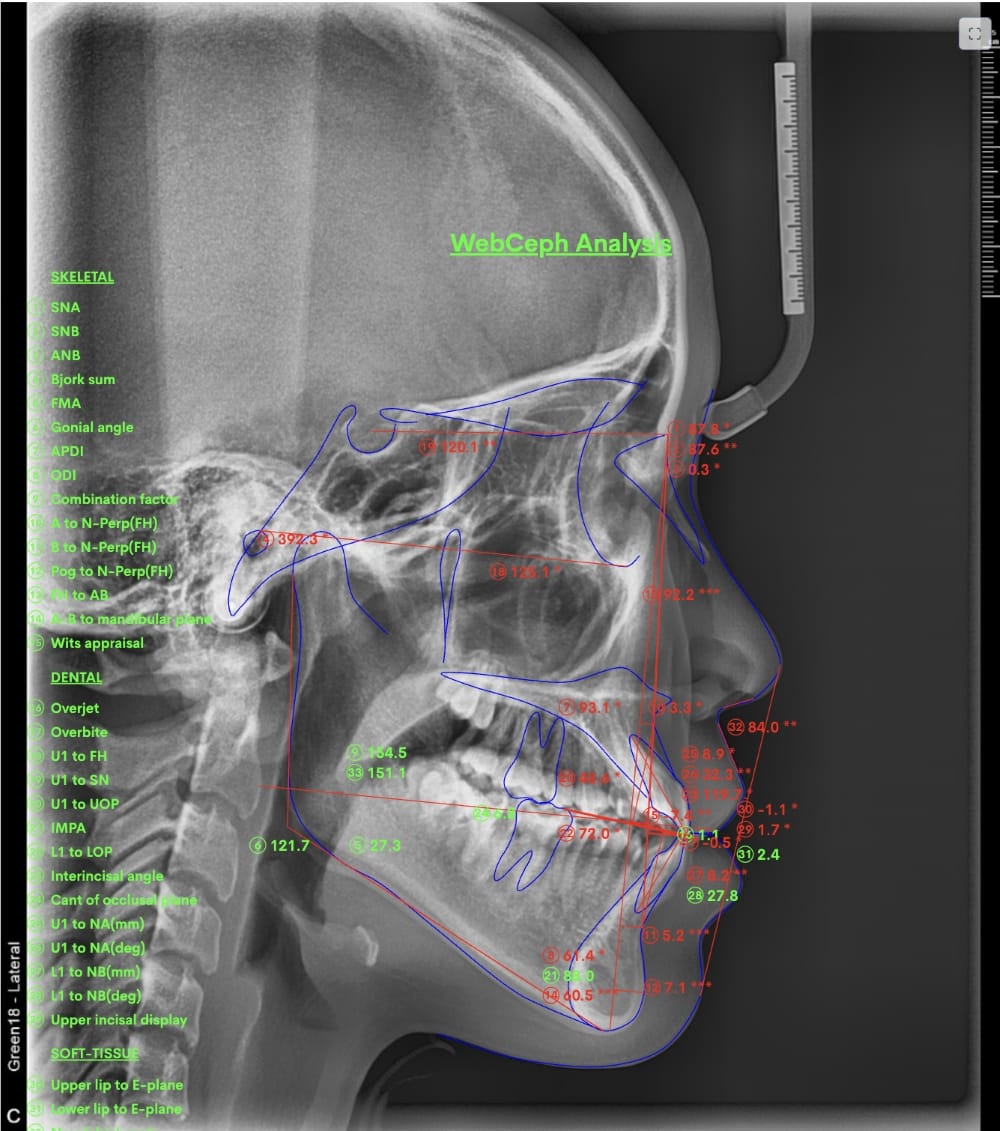

具体的には、口腔内写真やレントゲン写真、特にセファロX線写真を分析し、診断を行います。

例えばセファロX線写真での診断を行い上下の顎の位置のズレが大きいと判断した場合、歯列矯正のみでの治療は困難と判断し、外科的な手術をおすすめする場合もあります。

分析をしますと

- 骨格的な上下あごの前後差は中等度

- 噛み合わせの位置も下あごの奥歯が半分くらい前にズレていた

- 上の前歯が前に傾斜、下の前歯が内側に傾斜しているにもかかわらず、受け口

分析しますと

- 骨格的な上下あごの前後差は中等度〜重度

- 上の前歯が内側に傾斜している

- 骨格的な上下あごの前後差は重度